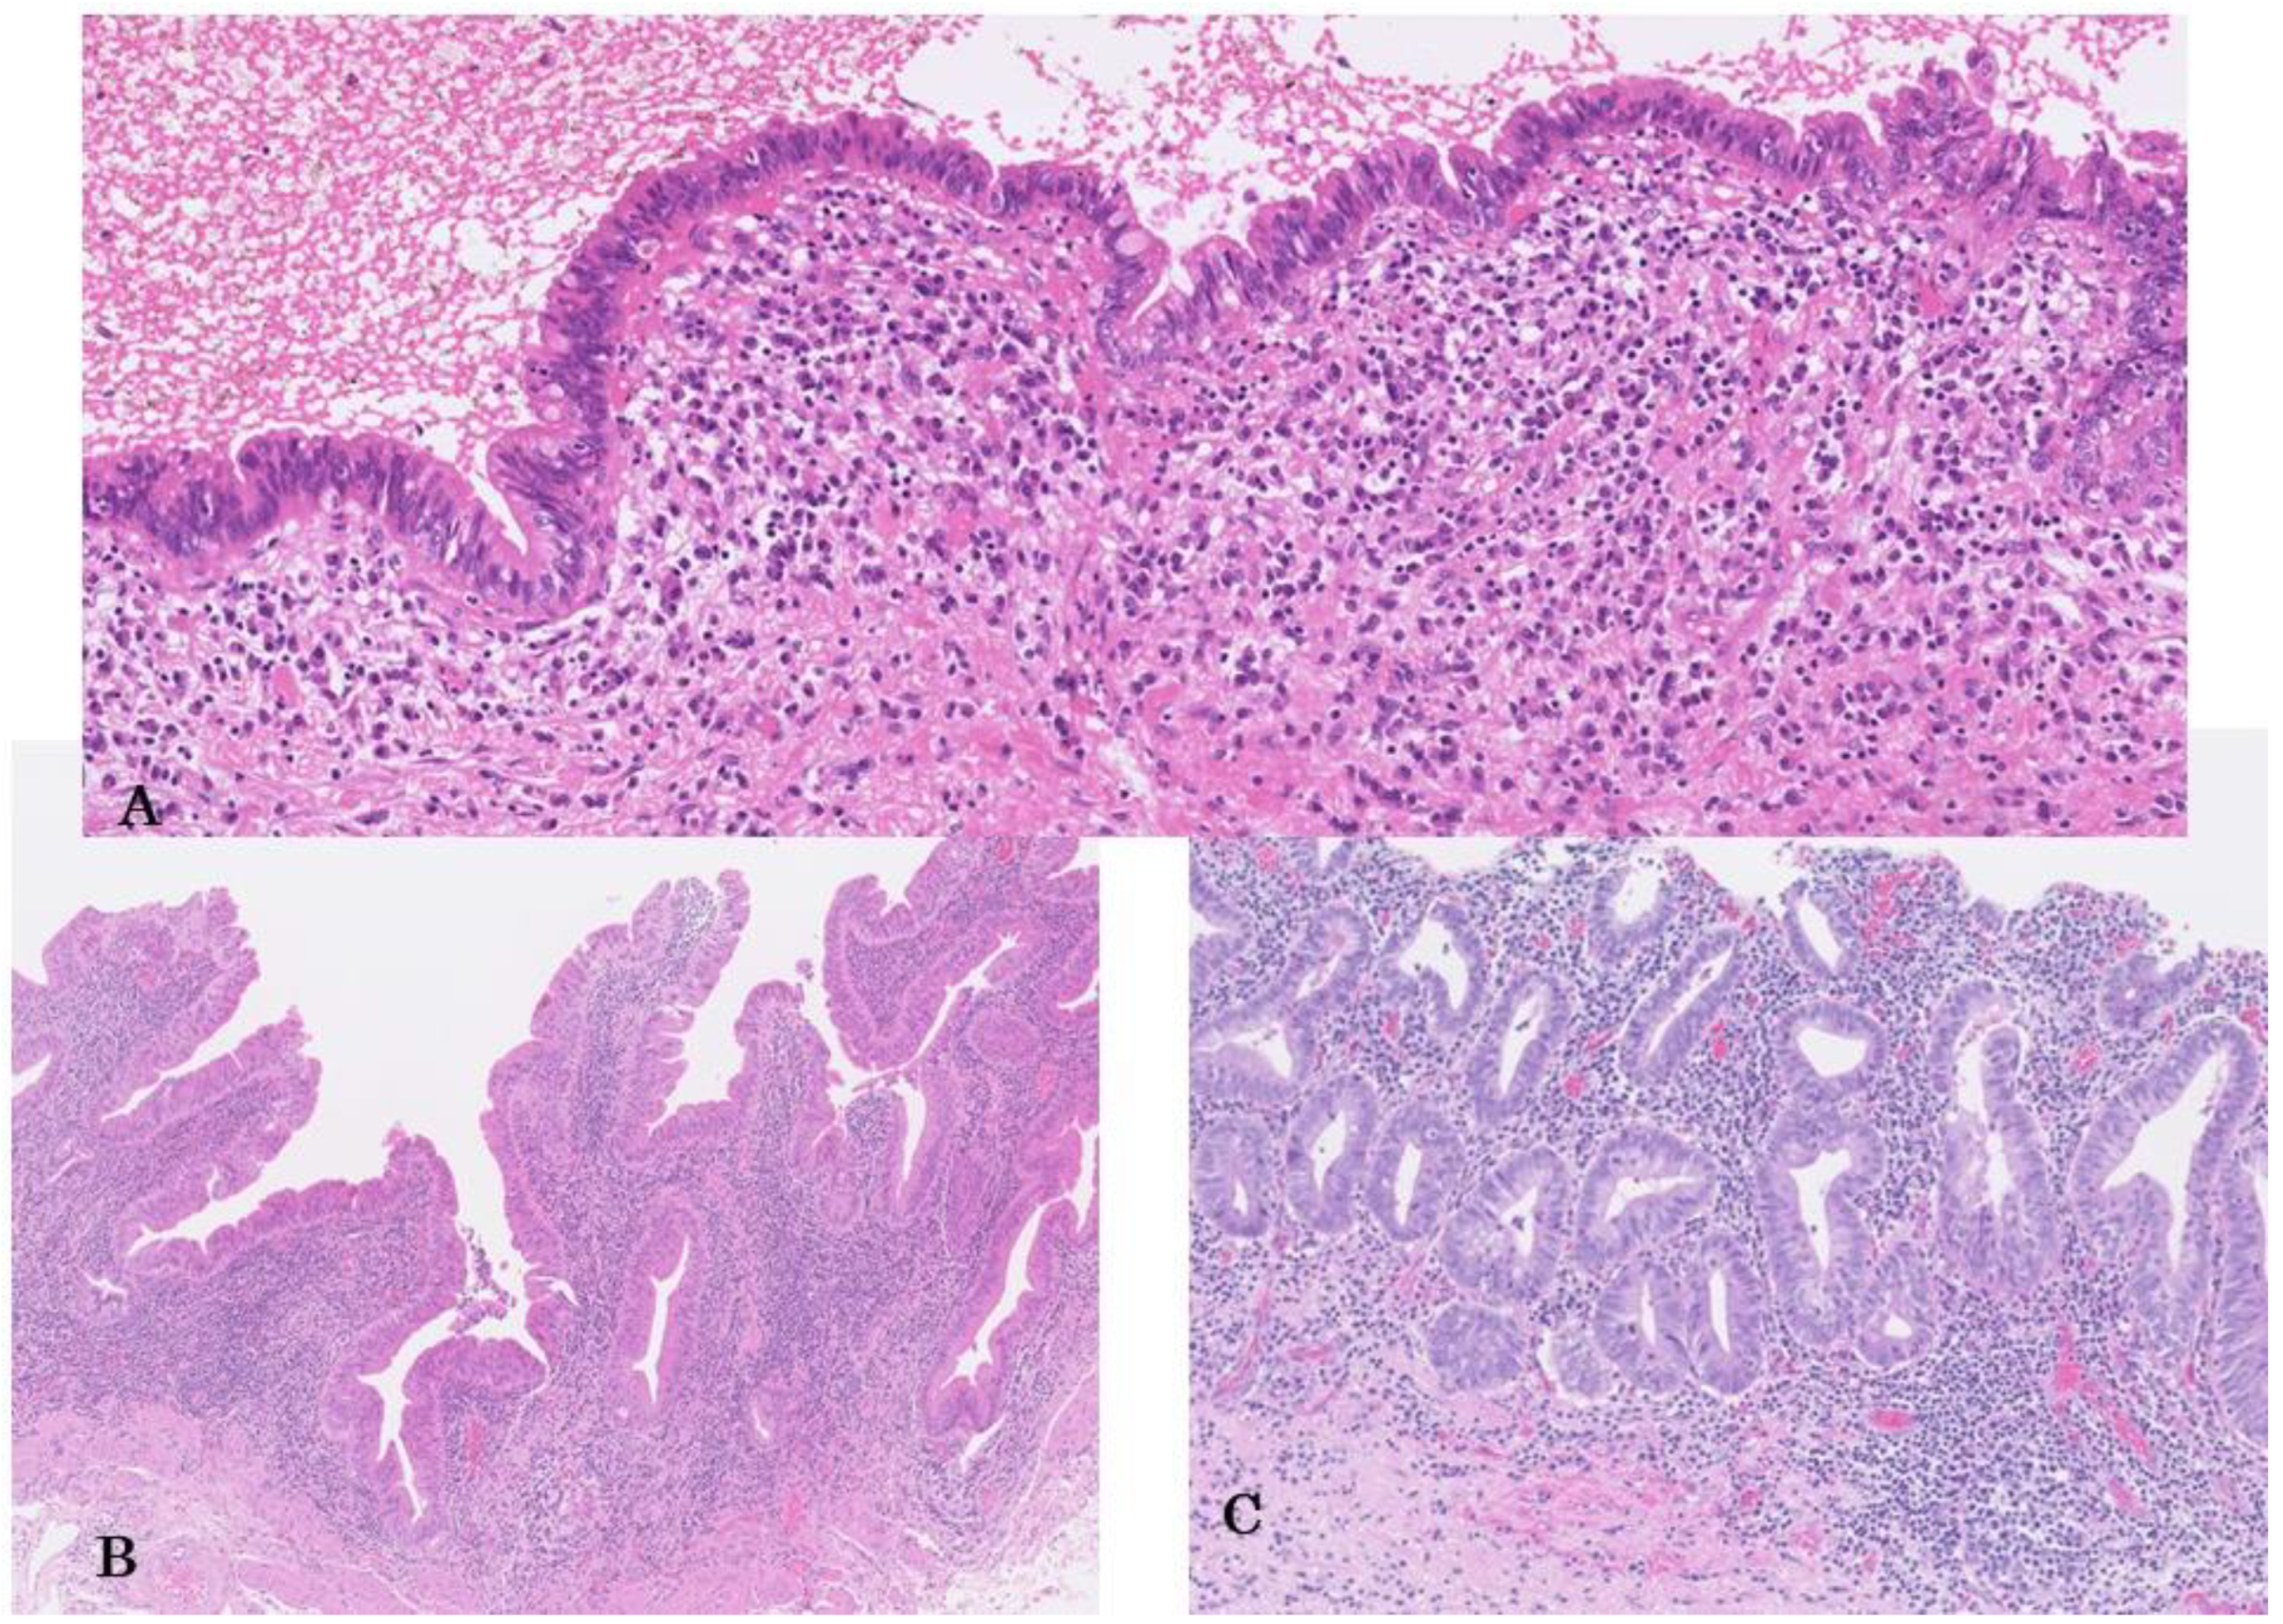

Histologically, their basic structures present with flat/pseudopapillary, or micropapillary patterns, and many high-grade BilIINs are associated with few fibrovascular connective tissues (Figure 1A,B) [1,4,82,83]. Micropapillary structures may reflect physiological short foldings or papillary structures inherent to the bile duct and gallbladder mucosa [34,71]. However, micropapillary patterns higher than the surrounding non-neoplastic mucosa, may reflect unique tumor-specific structures. The micropapillary pattern is multiple but less common than the flat pattern [71,80,84]. Furthermore, some high-grade BilINs show complicated lesions and bizarre cellular and nuclear changes, particularly among micropapillary components, thus reflecting a relatively aggressive characteristic [71]. However, even simple, flat, high-grade BilINs without architectural complexity may show progression [22]. The flat type is undetected during macroscopic examination, whereas the micropapillary type may be recognized by mucosal thickening, velvety texture and /or fine granular patterns [80,84].

Figure 1.

High-grade biliary intraepithelial neoplasm (high-grade BilIN); (A) Flat type. Lining epithelia of the extrahepatic bile duct show pseudostratified and hyperchromatic and swollen nuclei. Nuclear polarity is variably lost. ×300. HE staining. (B) Micropapillary type. Micro- and short- papillary structures are lined by neoplastic atypical epithelia. Gallbladder. ×80. HE staining. (C) Propria forming type. Atypical glands with mucosa propria formation, appearing as so-called intramucosal carcinoma of the stomach. Extrahepatic bile duct. ×100. HE staining.

Occasionally, high-grade BilINs present a thickened “mucosa” that appears as well-formed propria (fibrovascular connective tissue with inflammatory cells), which appears intramucosal carcinoma of the stomach (Figure 1C) [1]. This may represent intraepithelial involvement of pre-existing metaplastic glands with a propria layer with connective tissue in the bile duct and gallbladder mucosa by neoplastic cells. Otherwise, this may be a unique high-grade BilIN developed by the neoplastic transformation of epithelial lining that accompanies mucosa propria formation.